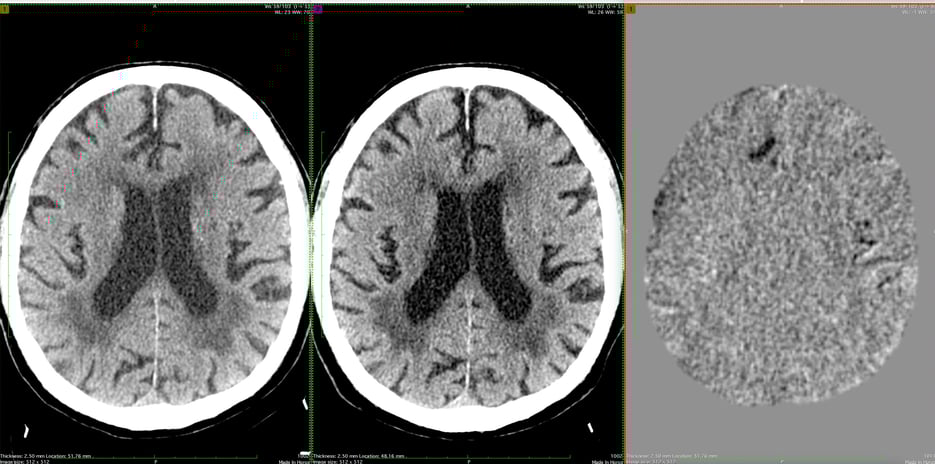

First panel original scans, second panel NeuroAlign images and third panel subtraction images (new minus old) showing enlarging SDH (upper image) and stable parenchymal hemorrhage (lower image).